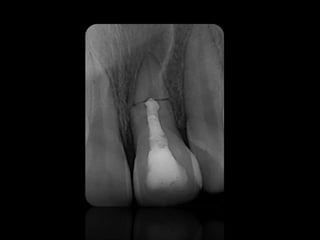

ABSCESO PERIAPICAL